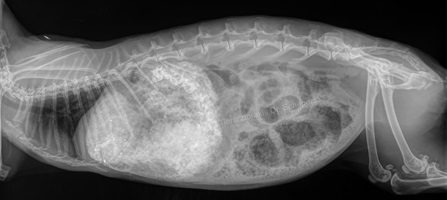

Röntgendiagnostik

Die sichere Diagnose wird durch ein Röntgenaufnahmen gestellt; hierdurch kann die Konsistenz des Mageninhalts (fest, flüssig, aufgegast) auch von weniger geübten Tierärzten sicher und objektiv beurteilt werden. Zudem besteht eine objektive Vergleichsmöglichkeit für spätere Verlaufskontrollen.

Die genaue Diagnose ist elementar für die anschließende Therapie:

• leerer Magen-Darm-Trakt, geschwächte Magen-Darm-Motorik, leichte Verstopfung => Zwangsfütterung notwendig

• Verschluss (mechanischer Ileus) oder massiv überfüllter Magen => Zwangsfütterung fatal!

Weiterhin kann objektiv beurteilt werden, wie groß der Magen tatsächlich ist, wie lange der Zustand bereits besteht (beim mechanischen Ileus v. a. anhand der Konsistenz des Mageninhaltes: anfangs homogen, anschließend "spiegeleiartig" durch beginnende Gasbildung) sowie inwieweit eine Magentympanie (= Aufgasung) beteiligt ist. Ein gewöhnlicher Kaninchenmagen ist rund, mit homogenem, strukturiertem Inhalt gefüllt und ragt maximal zu einem Drittel über den Rippenbogen hinaus.

Auch kann die Füllung des Magen-Darm-Trakts bereits einen deutlichen Hinweis auf einen Darmverschluss liefern: Bei dem typischen, im vorderen Dünndarmbereich lokalisierten Verschluss ist die Darmschlinge unmittelbar hinter dem Magenausgang leer und luftgefüllt, der dahinter befindliche Darm hingegen noch futtergefüllt.

Sitzt der Verschluss in einem anderen Darmabschnitt, kann der Darm zu größeren Anteilen mit Luft gefüllt sein oder gefüllte, stark dilatierte (= überdehnte) Areale aufweisen. In letzterem Fall kann der Magen (noch) eine normale Größe besitzen, da sich der Futterbrei zunächst im Dünndarm und erst später bis in den Magen zurückstaut.

Angeschoppte Köttel im Enddarm deuten auf eine dort befindliche Verstopfung hin.

Kontraströntgen

Insbesondere empfiehlt sich ein Kontraströntgen, um zwischen einem kompletten Darmverschluss und einer "nur" verlangsamten / erschwerten Darmpassage unterscheiden zu können, einen möglichen Verschluss genau zu lokalisieren (Grenze von Kontrastmittel zu Gas, Dicke der Darmschlingen) sowie Magenbezoare zu identifizieren.

Hierfür wird dem Kaninchen vom Tierarzt ein Kontrastmittel (Bariumsulfat oder eine jodhaltige Substanz) eingegeben, das erste Kontrollröntgen erfolgt nach 20-30 Minuten. Dabei kann beobachtet werden, ob und wie schnell sich das Kontrastmittel (und somit der Nahrungsbrei) durch den Magen-Darm-Trakt bewegt.

Nach 20-25 Minuten sollte das Kontrastmittel bereits deutlich sichtbar in den Dünndarm übergetreten sein. Nach spätestens 60 Minuten sollte es auch im Caecum sichtbar sein, nach 3-5 Stunden sollte es den kompletten Darm passiert haben.

Magenbezoare fallen dadurch auf, dass sie sich nicht mit dem Kontrastmittel anreichern. Stattdessen wird ein ausgesparter Bereich sichtbar. Die Übergänge zum kontrastmittelgefüllten Bereich sind meist fransig. In einem Magen, der frei von Haarballen ist, verteilt sich das Kontrastmittel hingegen vollständig und legt sich glatt den Magenwänden an.